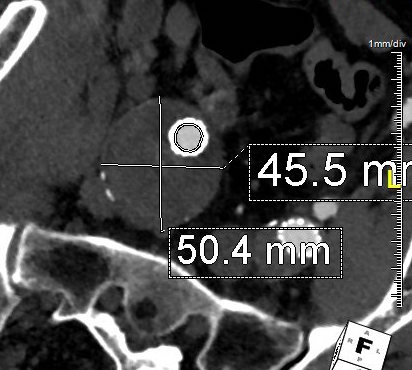

The diameter of the stent graft to be sealed to is measured and an area calculated. The sum of the areas of the two grafts to be placed need to equal or slightly exceed the area of this inflow stent graft. If you have decided the size of the external iliac graft, for example, then the diameter of other graft is merely a few geometric formulas away.

For example, take this patient who after EVAR of aortic aneurysm with AFX developed metachronous dilatation of the common iliac artery to 3.9cm with abdominal pain. The average diameter is 18.5mm. From the table, that rounds to 19mm corresponding to 283.53 square mm. If the internal iliac artery requires a 13mm graft, that is 132.73 square mm, the difference being 150.80 square mm. That corresponds to a 14mm diameter graft, but a slightly larger graft is preferred for oversizing. The external iliac artery is 8mm, and putting a 13mm Viabahn (largest available) in that would result in the B-infolding in the 8mm external iliac. Here, I bailed myself out by simply placing a 20mm AFX iliac limb extension, which by virtue of its design is resistent to infolding and tolerant of parallel grafts laid alongside in constricted channels. I found that the AFX iliac limb, a 20-13mm x 88mm length extension well suited for this.